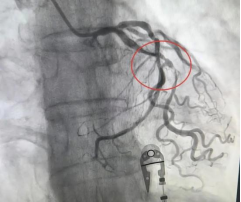

王女士,因“反复心累、胸闷5+年,再发伴头晕2小时”入院,入院后行冠状动脉造影检查,冠状动脉造影显示:LAD(前降支)中段弥漫性狭窄,最重处狭窄约90%,确诊为冠心病。随后,内科一病区医生团队为患者实施了冠状动脉支架植入术,术后,王女士的心累、胸闷症状明显缓解,困扰她的头晕也消失了。

(术前) (术后)